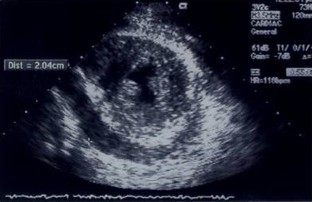

Fig. 2